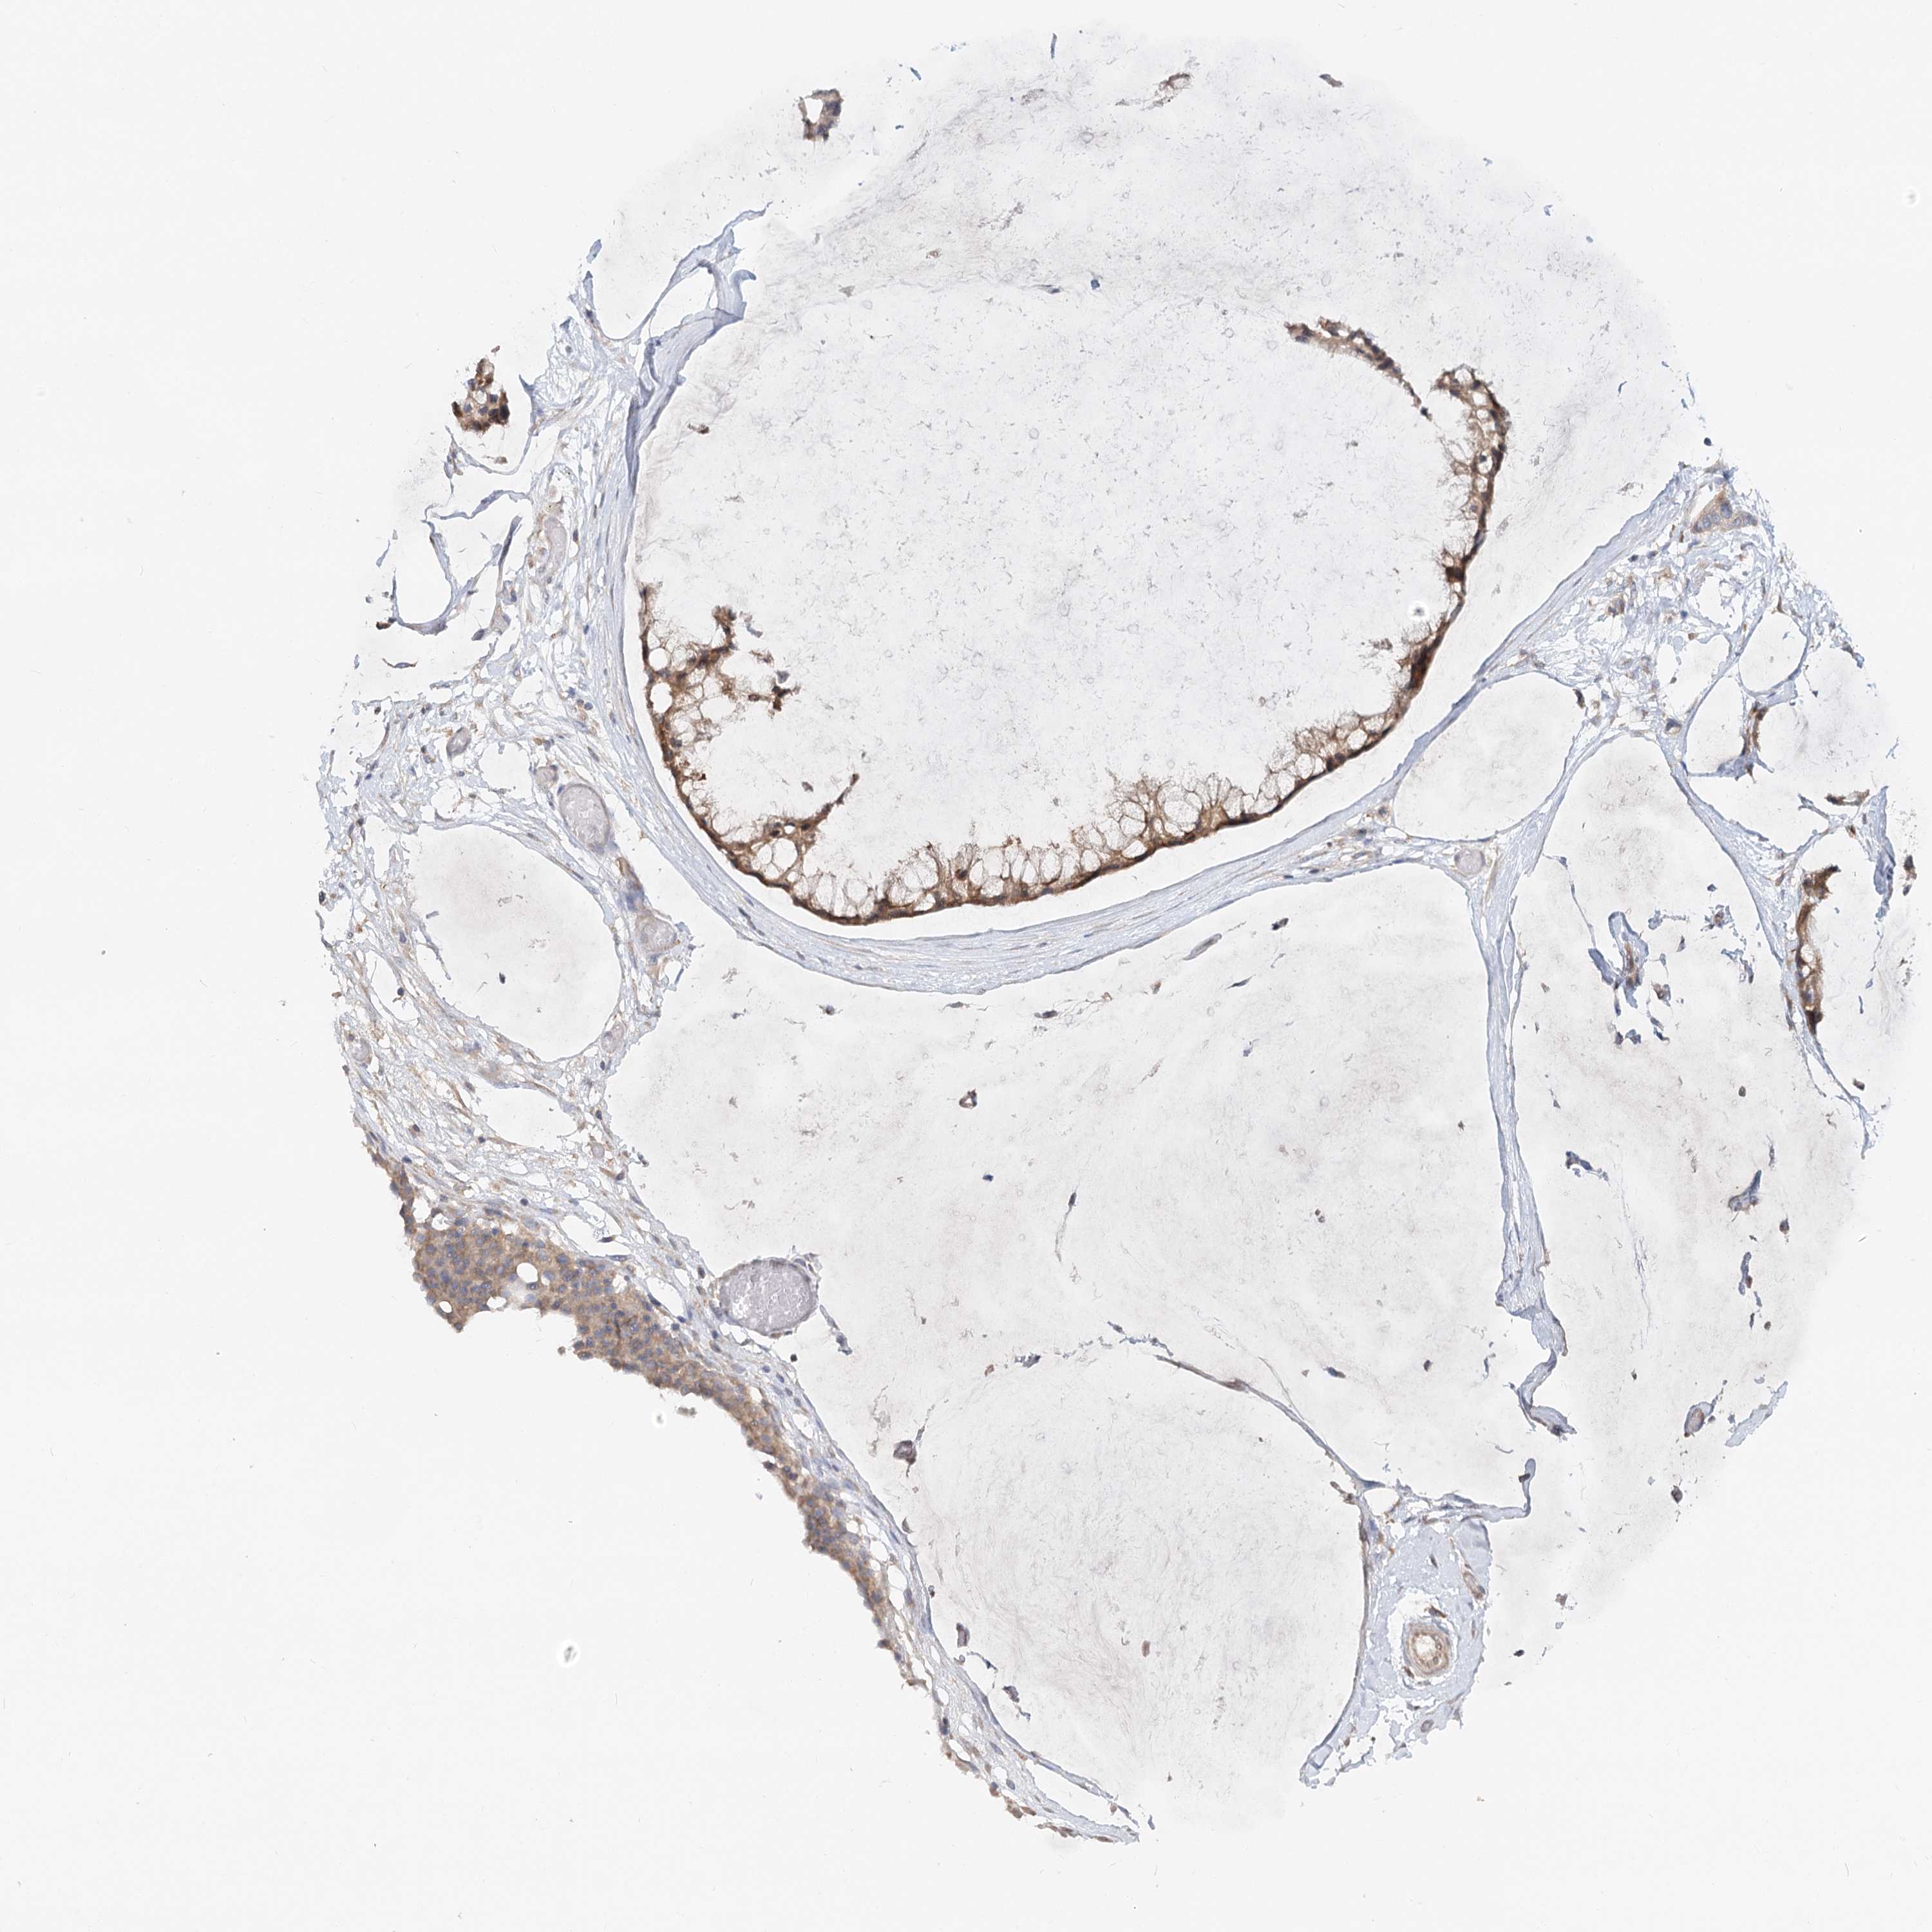

OVARIAN CANCER - Protein expressioni

A mouse-over function shows sample information and annotation data. Click on an image to view it in a full screen mode. Samples can be filtered based on level of antibody staining by selecting one or several of the following categories: high, medium, low and not detected. The assay and annotation is described here.

Note that samples used for immunohistochemistry by the Human Protein Atlas do not correspond to samples in the TCGA dataset.

Antibody stainingi

Antibody staining in the annotated cell types in the current human tissue is reported as not detected, low, medium, or high, based on conventional immunohistochemistry profiling in selected tissues. This score is based on the combination of the staining intensity and fraction of stained cells.

Each image is clickable and will lead to virtual microscopy that enables deeper exploration of all samples and also displays staining intensity scores, fraction scores and subcellular localization as well as patient and tissue information for each sample.

Antibody HPA035945

Antibody HPA056766

Antibody CAB037212

Staining

High

Medium

Low

Not detected

Cystadenocarcinoma, serous, NOS

Carcinoma, endometroid

Cystadenocarcinoma, mucinous, NOS

Carcinoma, NOS